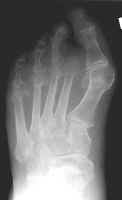

Second toe amputation with resultant hallux valgus

deformity. This is a common complication of second toe amputations and occurs

because the great toe tends to drift toward the third to fill the gap left by the

amputation.